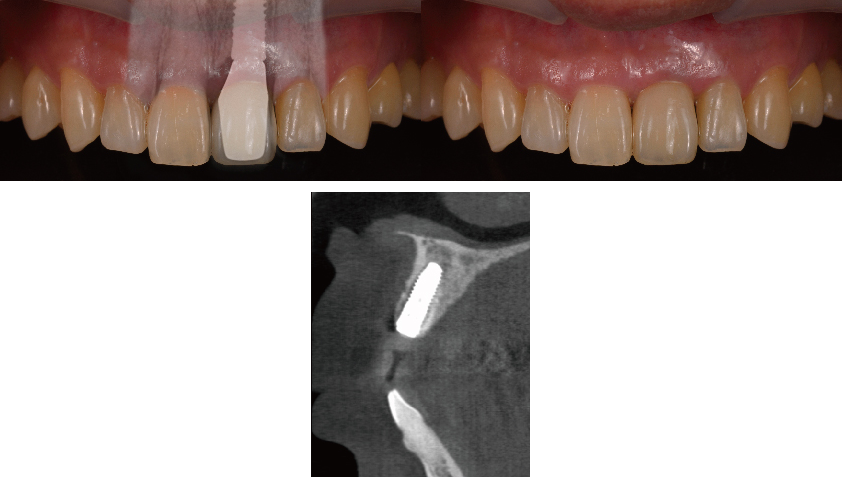

治療前のシミュレーション

施術前のレントゲン

サージガイドを使用することによって計画された位置に正確な施術が可能です

― 治療後 ―

計画した位置に正確に施術することで良好な審美結果が得られます

コンピューターガイデッドインプラント治療 + 歯科用顕微鏡を用いたマイクロサージェリー 審美的に良好な結果が得られています

当院では、コンピューターガイデッド インプラント治療で正確な位置にインプラント手術を行い、そして前歯などの審美領域では顕微鏡を使用したマイクロサージェリー(顕微鏡下手術)を行うことで傷跡の目立ちにくい自然な仕上がりのインプラント治療を行っています。